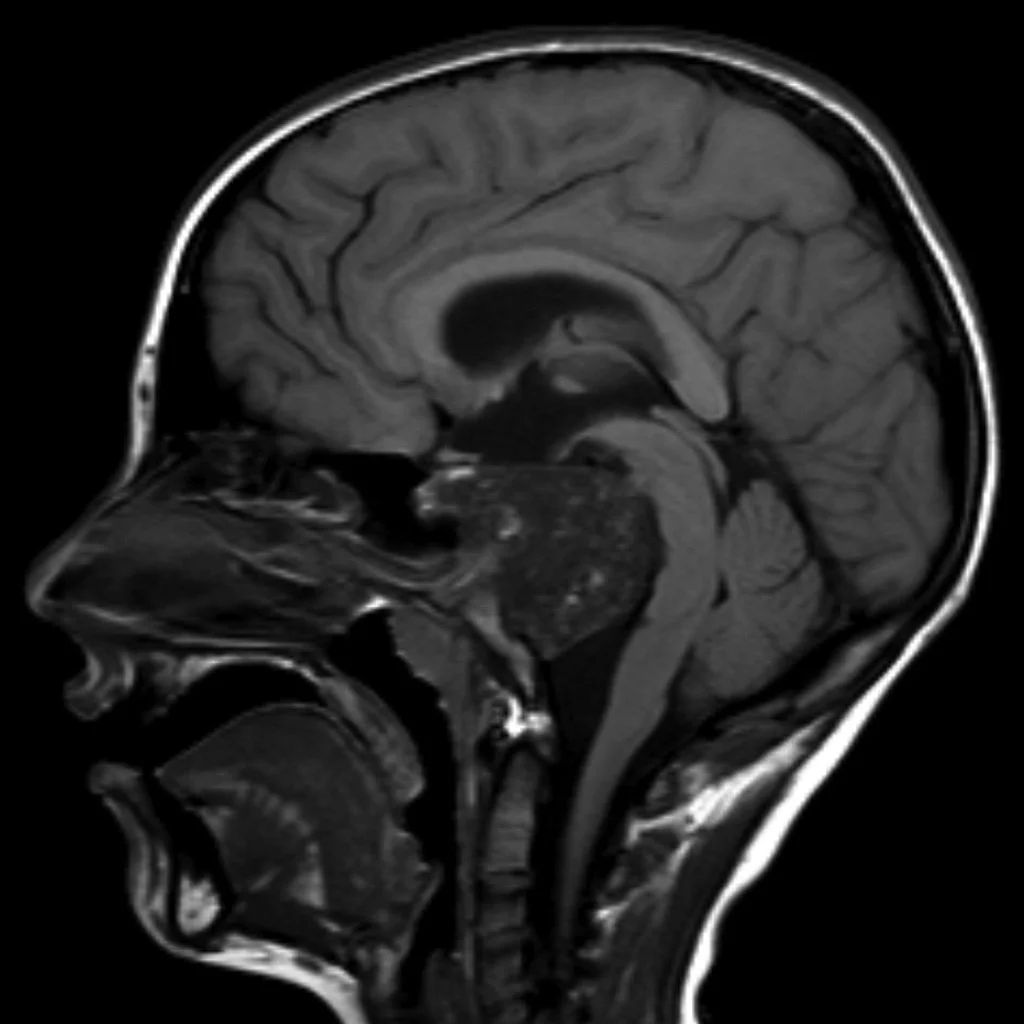

Chordoma

• Arise from notochord (therefore can arise anywhere from sacrum to sella)

• Locally aggressive bone mass

• Commonly present in spheno-occipital (near clivus) (young adults) or sacro-coccygeal (older adults) regions - typically in midline

• Thumb sign - the chordoma projects posteriorly causing mass effect on the anterior aspect of the pons as if your thumb was pushing it back

• Hyperattenuating and well circumscribed, may have intra-lesional calcifications (from erosion of local bone)

• MR:

• T1: low sign

• T2: high signal

• Typically septated

• T1 C+: heterogenous enhancement with honeycombing appearance